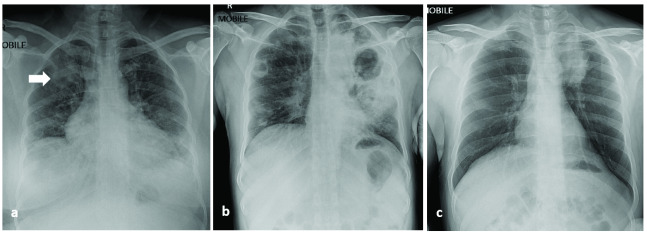

COVID-19 and <i>Mycobacterium</i> coinfection in Brunei Darussalam: case series.

COVID-19 and Mycobacterium coinfection in Brunei Darussalam: case series.